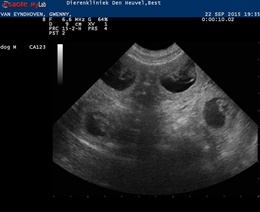

22 September 2015

And then it is time for the ultrasound. We have great news. She is very very very pregnant! We saw a lot of puppies!!

She already showed some signs of pregnancy but still it is always exciting to see if the ultrasound confirms our feeling.

Puppies are expected due 17 October 2015 . Her weight 17,8 kg.

Below you van see two pictures of the ultrasound: